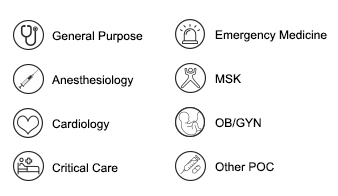

Wide Applications Scenarios

Higher integration and lower consumption. Cool design with powerful inside. Adaptable for any situation especially in general imaging and POC. The portability of this new-generation ultrasound system allows doctors to tackle more challenges and greatly improve their efficiency at work. CHISON SonoAir is the one you will never regret to choose.

General Purpose

Anesthesiology

Emergency Medicine

Critical Care

Physical Therapy

OB/GYN

Pediatrics

Other POC

VET